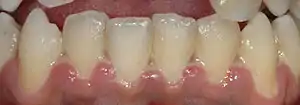

| A fairly mild presentation of acute necrotizing ulcerative gingivitis at the typical site on the gums of the anterior mandibular teeth. | |